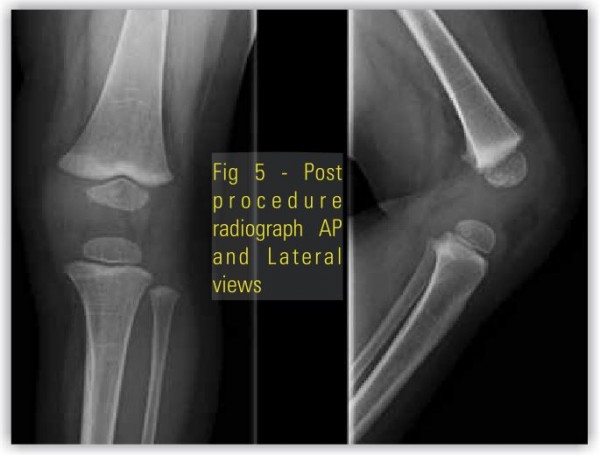

Our case was a preterm (35 weeks) baby boy born by normal vaginal delivery with history of oligohydraminios, presented with extreme hyperextension of left knee with toe almost touching the abdomen (Fig.1 ) with associated anomalies present; patient had CDH(Fig.3 and 4), Quadriceps contracture(Fig.2 ) and CTEV in the same involved lower limb. Left hip showed acetabular dysplasia. The affected left side shows presence of increase in depth of iguinal fold, abduction is limited at the left hip, the Ortolani and Barlow test was positive. Telescopic sign was positive. The feet on both side were inverted to about 30 degree and foot was pointing down wards. The ankle was in equines the feet were supinated and adducted, dorsiflexion beyond 90 degree was not possible. Tibia was normal and was not having an internal torsion. Passive stretching followed by above knee (toe to groin) POP splints was used from the first day. The basic principal of correction of adduction first followed by varus & then equines is followed. The splints were changed every seventh day with gradual bending. In about a month time knee flexion range of movement about 70 degree was achieved. There is need to be cautious at this time to avoid excessive & forceful correction as this may lead to damage to epiphysis & future growth abnormalities. As mentioned by Nogi et al, when there is concurrent presence of DDH with this knee abnormality then knee problem should be treated first as good knee movements can help with correction of hip abnormality [19]. In three months’ time, the left knee adopted a normal shape and position. The splints were discontinued and the mother was advised to continue passive stretching. The CDH was treated by abduction splints (wearing of double diapers) for six weeks. CTEV was treated with serial manipulation and POP Casts. A follow up at the age of one year showed normal position of both knees(Fig.5) as well as both hips.